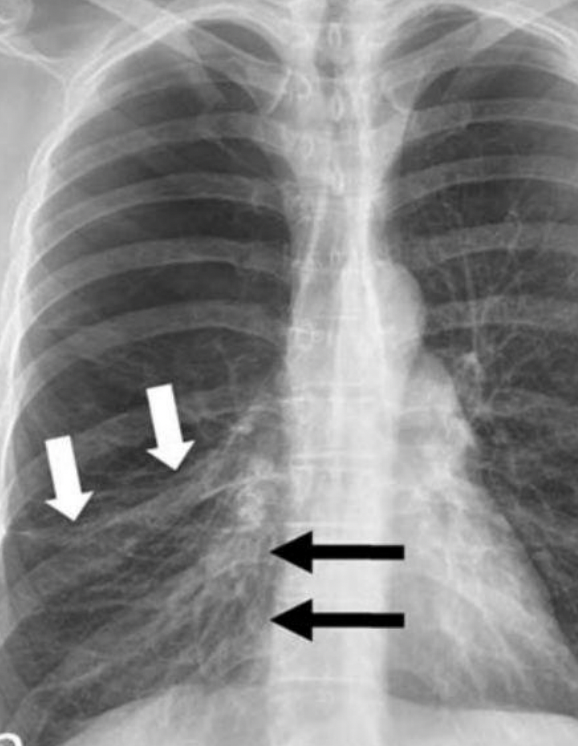

Bronquitis crónica

RX y Tc

Patron intesticial grueso

Imágen en riel o tranvía: inflamación de pared bronquial

Manguitos peribronquiales: engrosamiento visto de frente